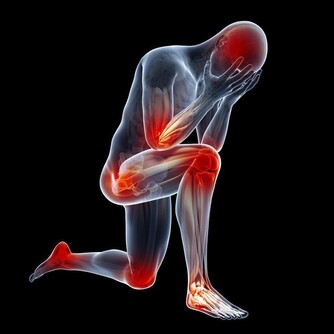

在晚上睡覺的時候,有不少的人出現了腿腳抽筋的現象,大部分的人都認為這種現像只是因為缺鈣引起的,

實際上,缺鈣是一種原因,當我們血液中的鈣濃度下降時,

進而就會引起神經肌肉的興奮性加強,這種現像從專業的角度叫作肌肉痙攣,

而往往最典型的表現就是腿腳抽筋,不管是夜晚還是在白天,都有可能出現。

這時候就需要我們日常的補些鈣片了,進而讓我們的血液中不再缺少鈣的成分,

但除了這種缺鈣的情況,腿腳抽筋還可能是以下這幾種原因,別大意!

腿腳抽筋可能是因為過度疲勞:

隨著人們生活物質的提高,但是對於相當一大部分的人群來說,身上的重擔也不少,

尤其是對於中老年人來說,長期處於一種體弱疲勞的狀態,

再加上自己在運動方面過於嚴格的規定,導致運動過度,讓機體產生了大量的代謝廢物。

到了晚上的時候還沒有緩解掉,那麼就容易引起腿腳抽筋的現象,

一般情況下,可持續的時間在十秒或者是數秒以上,影響我們正常的睡眠。